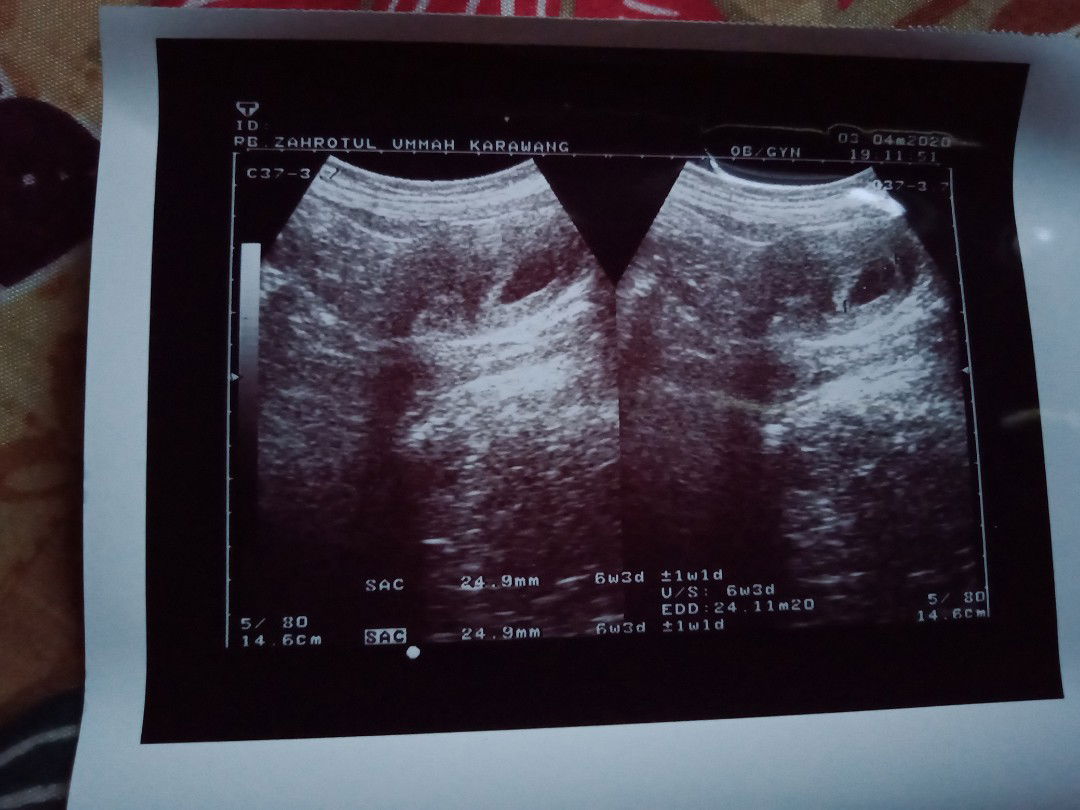

baby ga berkembng

Bunda Disni ada ga yang ke dokter atau bidan USG trus di kasih tau kalo hasil USG beda sama hitungan hpht Dan itu bedanya 2mngguan Takutnya janin TDK berkembang ( bo) Tp payudara membesar..mual seperti hamil normal... Saya riwayat keguguran 3x... Sedih ???bunda ... Menurut kalian saya harus gmn ya... Ada tau ga biar janin trus berkembang aku ingin sekali hamil dan punya anak lagi..hasil USG ku terbaru